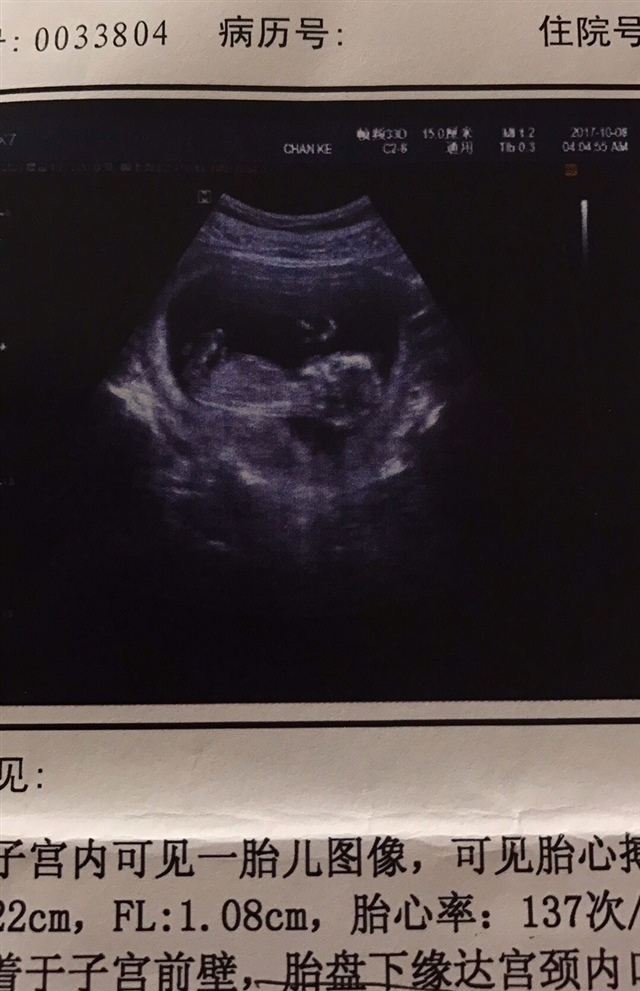

宝宝3个月

孕11周+3天

男孩

孕8周+3天

像男孩

孕16周+6天

看着是男孩

蓉

孕6周+4天

应该是男的